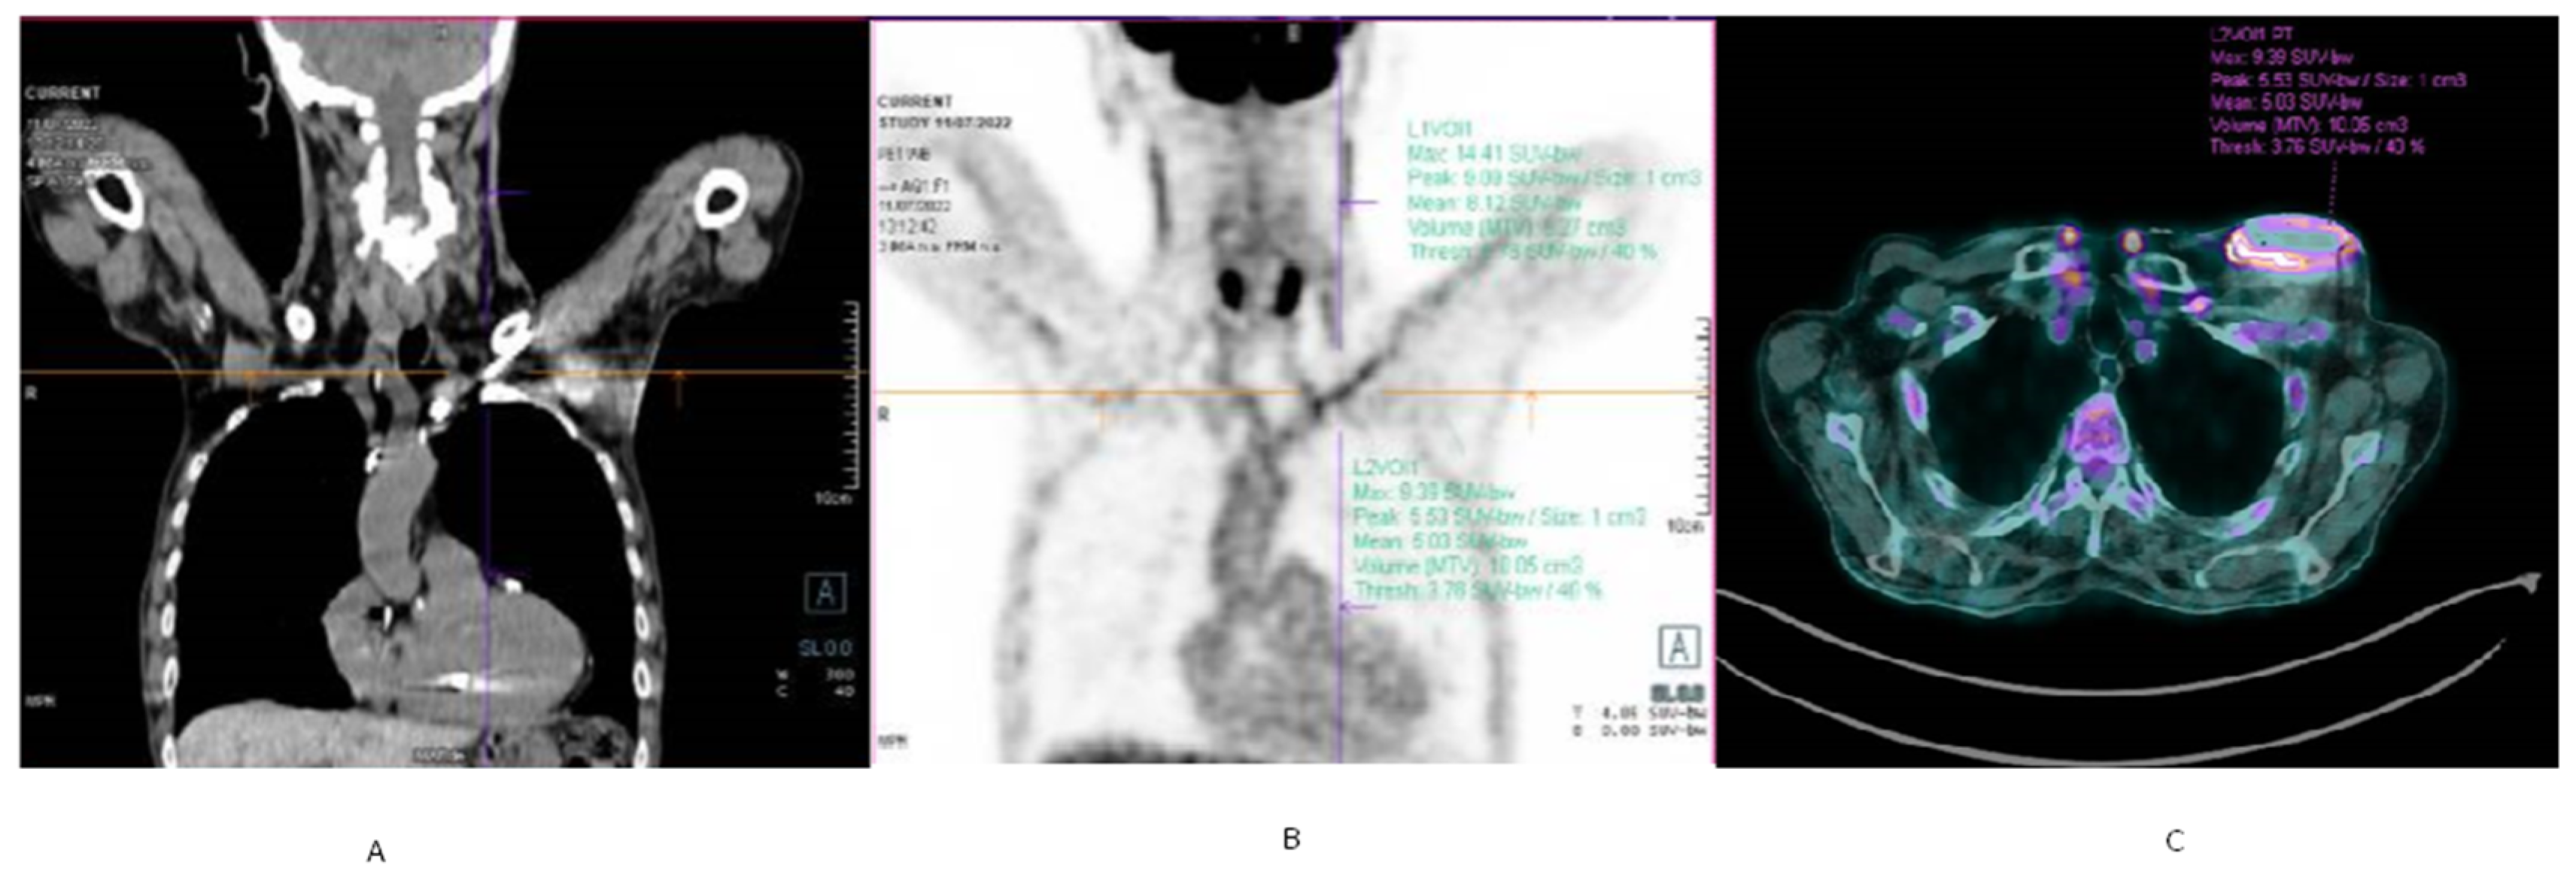

- Ten Hove, D.; Slart, R.H.J.A.; Sinha, B.; Glaudemans, A.W.J.M.; Budde, R.P.J. 18 F-FDG PET/CT in Infective Endocarditis: Indications and Approaches for Standardization. Curr. Cardiol. Rep. 2021, 23, 130. [Google Scholar] [CrossRef] [PubMed]

- Juneau, D.; Golfam, M.; Hazra, S.; Zuckier, L.S.; Garas, S.; Redpath, C.; Bernick, J.; Leung, E.; Chih, S.; Wells, G.; et al. Positron Emission Tomography and Single-Photon Emission Computed Tomography Imaging in the Diagnosis of Cardiac Implantable Electronic Device Infection: A Systematic Review and Meta-Analysis. Circ. Cardiovasc. Imaging 2017, 10, e005772. [Google Scholar] [CrossRef] [PubMed]

- Cautela, J.; Alessandrini, S.; Cammilleri, S.; Giorgi, R.; Richet, H.; Casalta, J.P.; Habib, G.; Raoult, D.; Mundler, O.; Deharo, J.C. Diagnostic Yield of FDG Positron-Emission Tomography/Computed Tomography in Patients with CEID Infection: A Pilot Study. Europace 2013, 15, 252–257. [Google Scholar] [CrossRef]